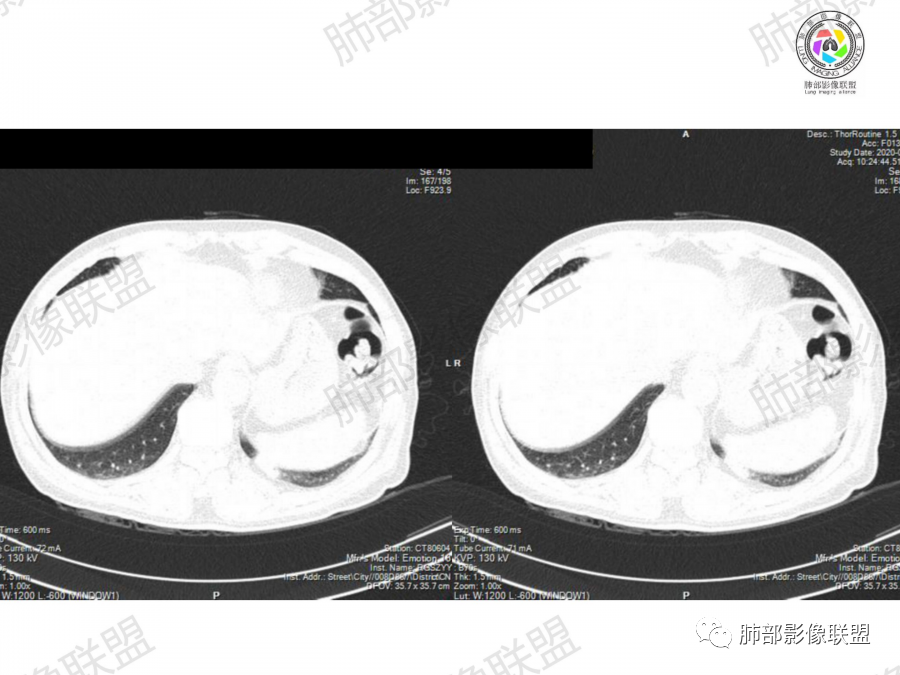

晨读:左肺下叶胸膜下实性结节影边缘毛糙,有毛刺,分叶,近段支气管未见显示,可能堵塞,远端宽基底与胸膜相贴,边缘平直,部分彭隆,病灶局限、单发,无增强,不好判断肿瘤血供,临床男性,63岁,无症状,体检发现,有吸烟史,考虑恶性:腺癌,鳞癌,小细胞肺癌,鉴别:肺隐球菌建议增强及穿刺检查。

晨读病例,老年人 ,吸烟史,左肺下叶结节影,密度均匀,边缘毛糙,周围可见长毛刺,病灶边缘分叶,局部膨隆,部分边界平直,收缩,病灶相邻胸膜处可见糊墙征象,病灶近肺门处见支气管堵塞,考虑恶性病变,周围型肺癌:鳞癌伴肺不张>腺癌,鉴别隐球,炎性假瘤。

细、长、软毛刺

边缘模糊,支气管关系不明确

糊墙,胸膜下脂肪间隙明显增厚

边缘平直为主,部分膨隆,糊墙征

密度比较均匀;

总体倾向炎性,不除外肿瘤。